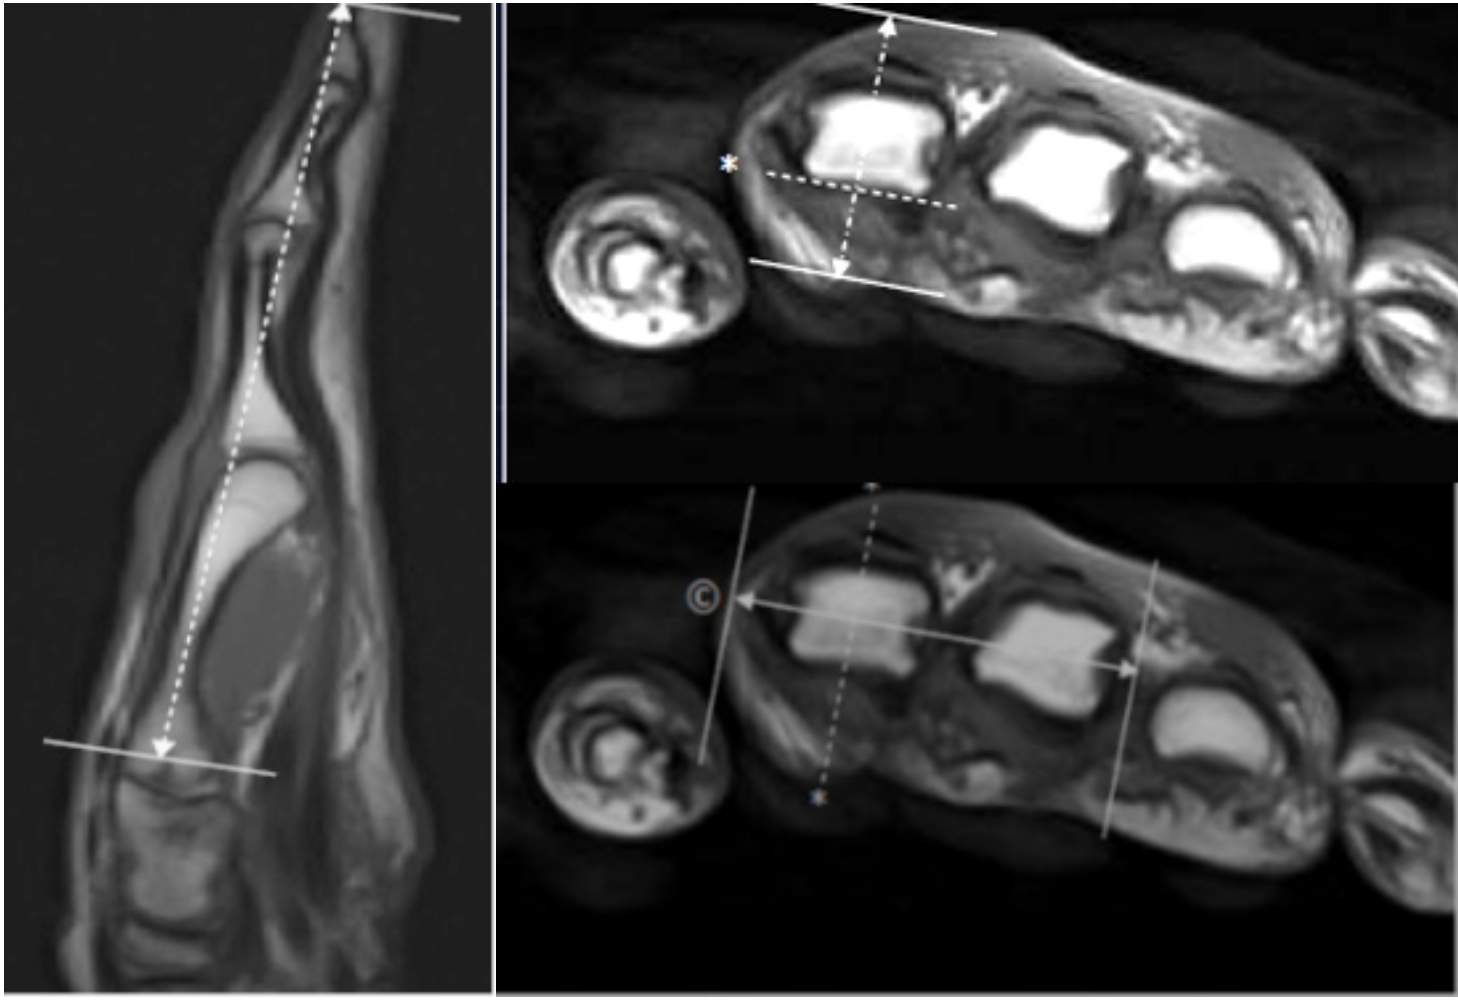

3T Resonance Imaging of the Thumbnormal Appearances and

Coronal T2 weighted fatsuppressed MRI of the thumb demonstrating the Coronal Mri Thumb Planning The planes of section (sagittal, coronal, and axial) must be aligned to the digit of interest; 11 rows use flex or head coil. Align the planning block parallel to the. Plan the thumb coronal localizer on the hand coronal localizer. The planes of section (sagittal, coronal, and axial) must be aligned to the digit of interest; Use rest slab proximal. Coronal Mri Thumb Planning.